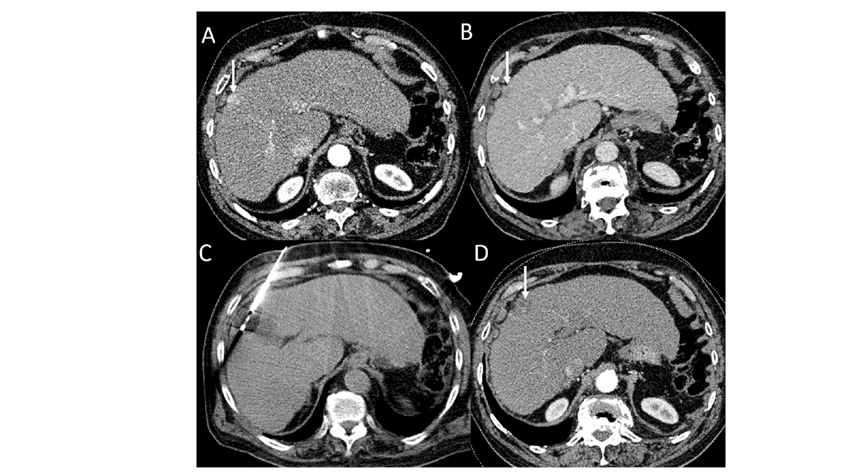

(A)動脈期CT圖像顯示有一個包膜下結節(jié)(箭頭)。(B)門靜脈期CT圖像顯示病灶區(qū)(箭頭)。(C) 在手術過程中的CT顯示一個冷凍探針位于病灶內(nèi)。患者在手術及住院期間無并發(fā)癥及重大并發(fā)癥發(fā)生。隨訪時間中位數(shù)為7個月(范圍:3-12個月),隨訪期間患者無局部腫瘤進展或死亡。

(A)門靜脈期 CT 圖像顯示膽囊附近有病變(箭頭)。(C) 手術過程中CT 顯示冷凍探針位于病灶內(nèi)。(D)消融手術后 1 個月CT 顯示完全消融。

本研究中患者隨訪期間無局部腫瘤進展,無死亡病例,沒有發(fā)現(xiàn)與手術相關的并發(fā)癥。證實冷凍消融是一種有效的治療方式,在技術上是可行和安全的。由于肝包膜下病變位置特殊,射頻消融有出血及腫瘤種植的風險,可能會對鄰近器官造成損傷,并且增加局部腫瘤進展的風險。近年來,冷凍消融術的應用逐漸廣泛,有研究顯示冷凍消融治療具有明顯優(yōu)勢,可治療特殊部位的肝腫瘤。本研究的目的是評價冷凍消融治療肝包膜下腫瘤的安全性和有效性。回顧性納入2016年7月1日至2018年9月1日期間冷凍消融的57例患者。包括42例男性和15例女性,平均年齡為62.4歲(范圍:48-82歲)。每個患者有1個或2個平均腫瘤尺寸為2.4cm的病變(范圍:0.6-4.0cm)。所有患者均患有慢性肝病或肝硬化,并伴有乙型肝炎(n=52)、丙型肝炎(n=3)和其他肝炎(n=2)。根據(jù)腫瘤位置,在膈肌或肝臟下附近有18個病變(26.5%),胃或腸附近有9個病變(13.2%),腹壁附近有33個病變(48.5%),腎臟附近有8個病變(11.8%)。